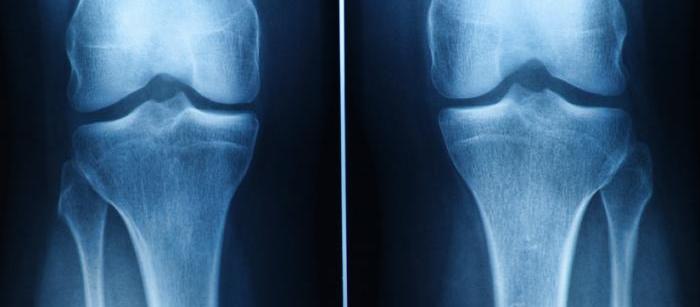

Treatment Options for Cartilage Damage

Current treatments focus on symptom relief or joint replacement for severe cases.